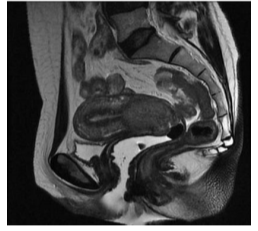

Paciente de 45 anos queixa-se de sangramento genital quase que diariamente há 1 ano. Refere também dor pélvica com irradiação lombar. Sem vida sexual ativa no momento. Antecedentes obstétricos: 2G 2P normais. Tabagista 1 maço dia. Ao exame especular observava-se o colo com orifício externo irregular e sem lesão macroscópica aparente na exocérvice. Ao toque retal os paramétrios estão livres. Exame de citologia cervico-vaginal com resultado compatível com lesão intra-epitelial de alto grau e biópsia do colo com diagnóstico de adenocarcinoma in situ. A figura representa o exame de ressonância magnética de pelve.

Em resumo, temos uma paciente com sangramento genital e dor lombar, sintomas que devem chamar nossa atenção. Na nossa investigação, foi encontrada um achado de adenocarcinoma in situ, mas com exame físico do colo aparentemente normal. Mas se avaliamos a nossa ressonância, vemos uma lesão de dimensões razoáveis no colo uterino e se estendendo até para o corpo uterino, percebem? Veja na imagem a abaixo a lesão circundada em vermelho:

Portanto, temos uma dissociação entre o anatomopatológico, de uma neoplasia não invasiva, da imagem, que mostra uma lesão aumentada de tamanho e acometendo todo o colo do útero, e por que não também da clínica com dor lombar associada (possível sinal de doença mais avançada)?

Dessa forma, é imprescindível obtermos uma amostra tecidual que seja compatível com a nossa suspeita clínica, o que não temos até agora – e a principal opção para tal é a conização, que permite a retirada de uma amostra tecidual maior. Mesmo que não tivéssemos a ressonância, a conização para amostra tecidual completa seria essencial na condução desse caso.